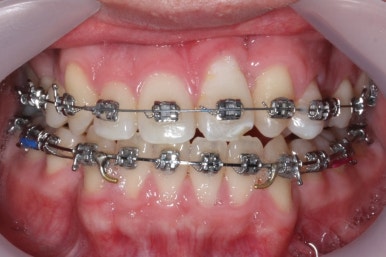

부산구순구개열 키다리아저씨치과에서 교정치료 하신지 1년여만에 드디어 앞니는 거꾸로 넘어왔고, 윗니들도 상당히 많이 가지런해졌습니다.

이 뽑은 자리도 상당히 많이 줄어든 것을 볼 수 있고, 이제는 정상적인 포개짐이 만들어졌습니다.

아래 치열은 거의 완료가 되었네요.

이 뽑은 자리도 다 없어졌고요. 대신 윗니는 어금니쪽에 약간의 틈과 기울어진 경사 등등 디테일한 조절을 계속해 나갑니다.

가장 최근의 사진입니다.

아직 치료 종료는 안되었으나 약간의 조절을 더하면 치료를 마무리할 수 있을 것 같습니다.

물론 윗니 한 쪽은 작은 앞니가 없고 한 쪽은 작은 어금니가 없기 때문에 중앙선이 100% 일치하지는 못하겠지만 기능적으로나 미적으로나 매우 개선되었음은 틀림없습니다.